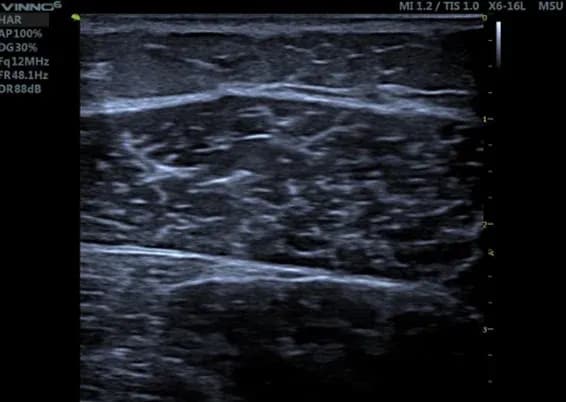

Ermüdungsbruch am Mittelfuß

Diese subtile Veränderung eines beginnenden Ermüdungsbruchs war zum Zeitpunkt der Diagnosestellung im Röntgenbild nicht sichtbar, wurde dann aber in der MRT bestätigt.